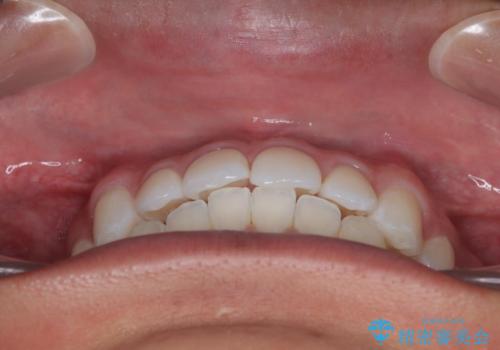

- 前歯のデコボコを気にして来院された患者様です。

あっという間に歯列が整い、目立っていた銀歯もなくなり、清潔感のある口元になりました。